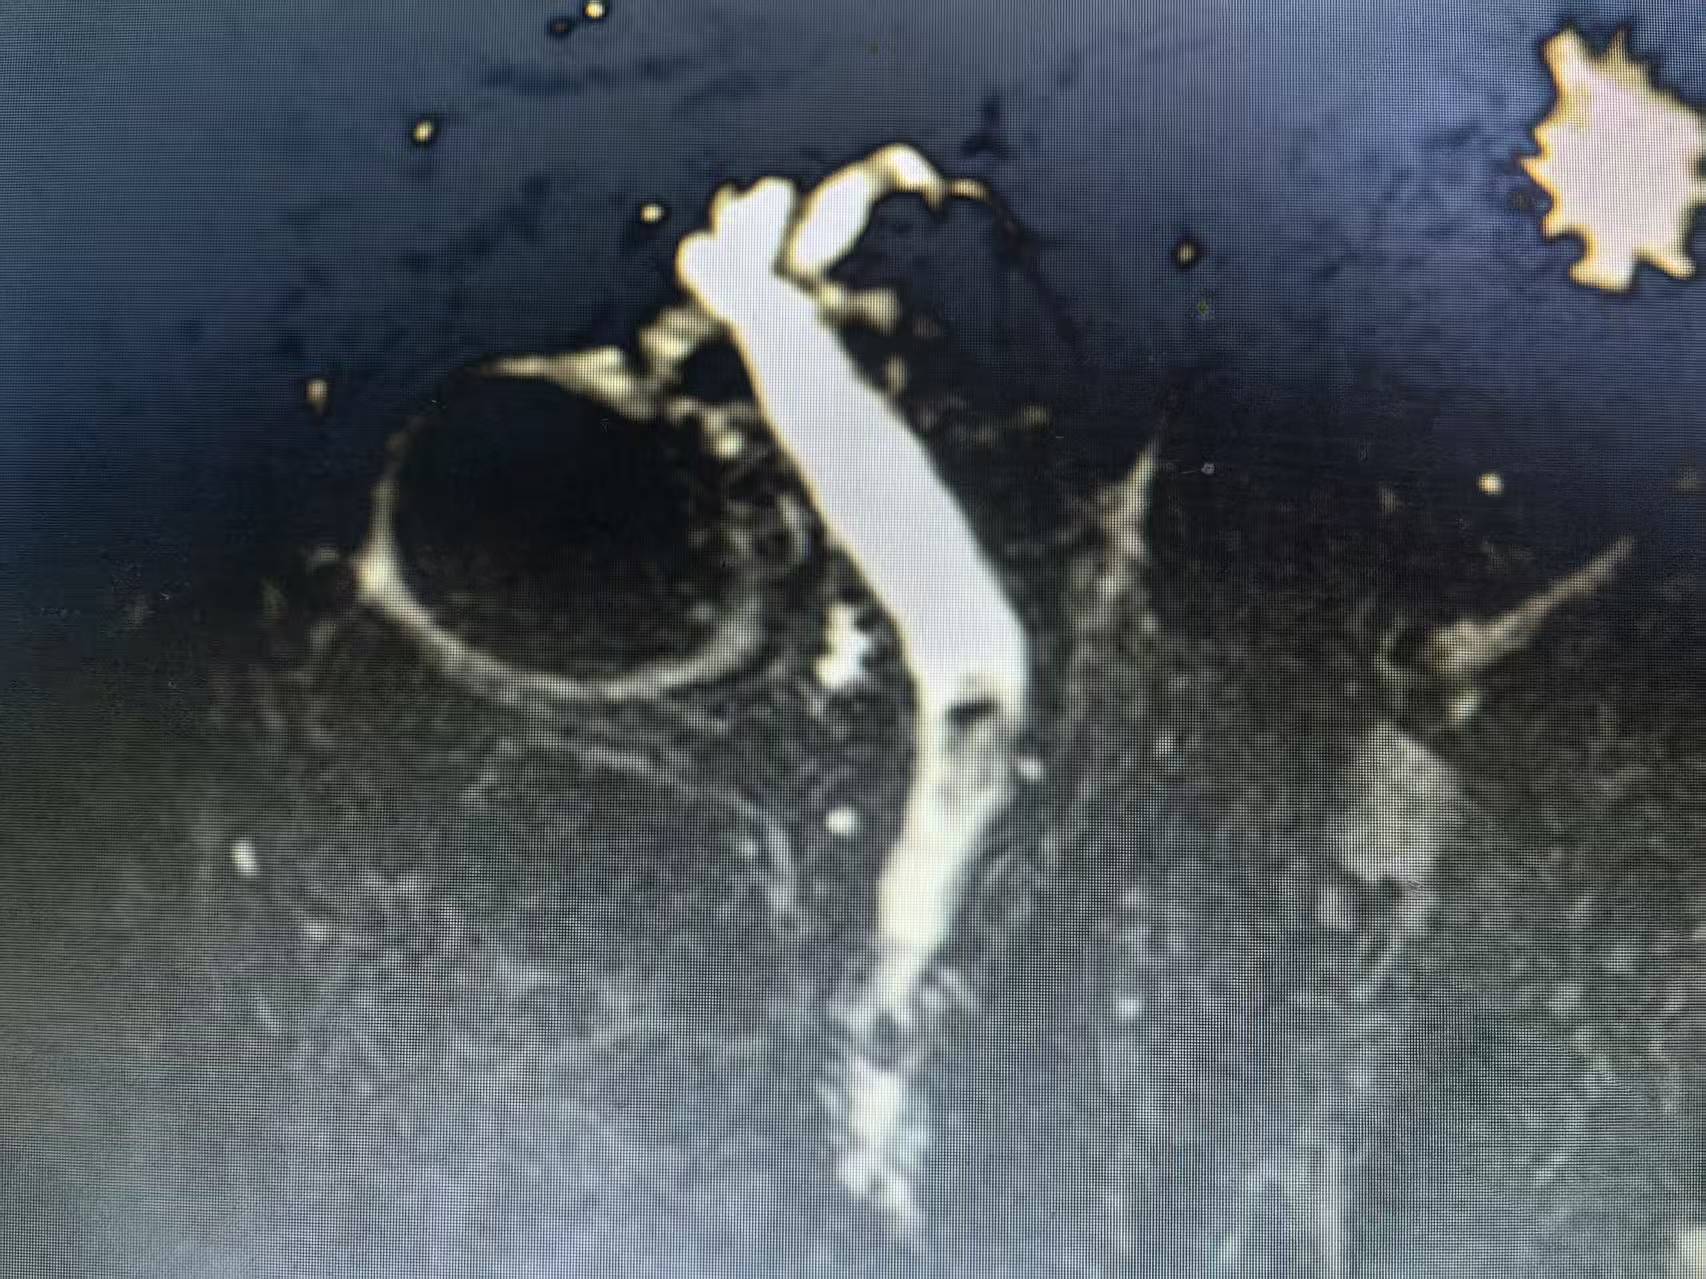

MRCP提示胆总管结石